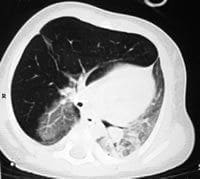

Figuras 2 A, B, C y D. TCAR en inspiración (izquierda) y espiración (derecha). Sobreinsuflación del lóbulo superior derecho

con hipovascularidad y desplazamiento contralateral de las estructuras mediastinales.

En los cortes en espiración las alteraciones descritas son más evidentes.